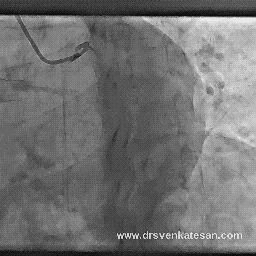

It was in 1980 , a dramatic concept was conceived . Why not use the esophagus as an access for pacing the heart

after all , it reaches as close as possible to the heart !

- The most important limitation is it can pace only the atria with high degree of success.

- Ventricular pacing is not that successful for the simple reason esophagus is anatomically insulated by the atrial chambers.

- Tran gastric positioning may reach the basal aspects of Left ventricle , but the threshold needed is too high that will invariably cause discomfort.This can be used in a dying patient when there is no other option .